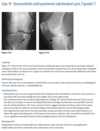

23

Four elderly patients with pain

An anteroposterior view of the pelvis

(Fig. 2.24.1) in an elderly man shows extensive thick-

ening of the right iliopectineal line (arrows) with

coarsening of the trabecular pattern and increased

sclerosis throughout the entire right hemipelvis.

Paget disease (i.e., osteitis deformans)

disordered bone

remodeling affecting osteoblastic and osteoclastic

activity. Osseous involvement may be monostotic

or polyostotic, and 80% of the patients are asymp-

tomatic at the time of the discovery of the disease,

usually as an incidental finding on radiography or

because of elevated serum alkaline phosphatase and

elevated serum and urinary hydroxyproline.

stage I (acute phase), active and unbalanced osteo-

clastic bone resorption usually causes areas of lytic

bone destruction. In stage II (intermediate phase),

increased osteoblastic activity results in thickening of the cortex, coarsening of the trabecular pattern,

generalized bone overgrowth, and loss of corticome-

dullary differentiation. In stage III (late or inactive

phase), there is a diffuse increase in the density of

involved bone. Stage IV is the superimposed malig-

nant degeneration of Paget disease into a osteosarcoma.

radiographic findings in the acute phase are

osteoporosis circumscripta, in which an advancing

lytic area is seen in the frontal or occipital regions of

the skull, and subarticular osteolysis in the diaphy-

ses of the tubular bones, especially the tibia, yield-

ing a flame-shaped or “blade-of-grass” appearance

(Fig. 2.24.2). In the intermediate stage, there may

be bowing of the long bones, an “ivory” or “pic-

ture frame” vertebral body (Fig. 2.24.3), and more

extensive calvarial osteosclerosis superimposed on

a background of osteolysis, resulting in the cotton-

wool appearance of the skull.

In the long bones of the lower extremity, corti-

cal thickening, increased trabecular coarseness, and

bowing can be seen (Fig. 2.24.5), and CT can confirm

these findings (Fig. 2.24.6).

MRI can be used to detect malignant sarcomatous de-

generation by showing new bone destruction, soft-

tissue masses, and bone and soft-tissue edema.